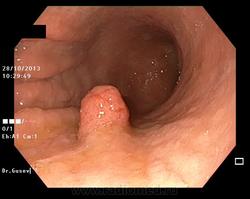

Больная В. 38 лет Диагноз: «Карциноид тела желудка малых размеров 11х9мм» (подтверждён гистологически).

6.- Гастроскопия. Фото представлены с разрешения доктора эндоскопического отделения ГБУЗ ЯО «ОКОБ» Д.В. Гусева.

Гастроскопия в режиме узкоспектральной эндоскопии (NBI)